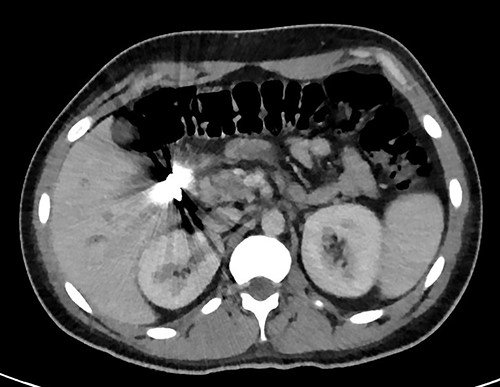

A full lab panel was ordered and revealed a total bilirubin of 1.1, direct bilirubin 0.5, lactate dehydrogenase 196, alkaline phosphatase 80, aspartate transaminase 46 and alanine transaminase 58. A computed tomography (CT) angiographic scan of the chest, abdomen and pelvis revealed the presence of a rim enhancing fluid collection in hepatic segment V with internal gas and containing a metallic foreign body, measuring 8 × 5 cm and consistent with abscess formation (Figs 2–4). The linear tract of the bullet in the right iliac crest was visualized in the CT as well.

Coronal plane of CT showing the retained bullet and hepatic abscess.